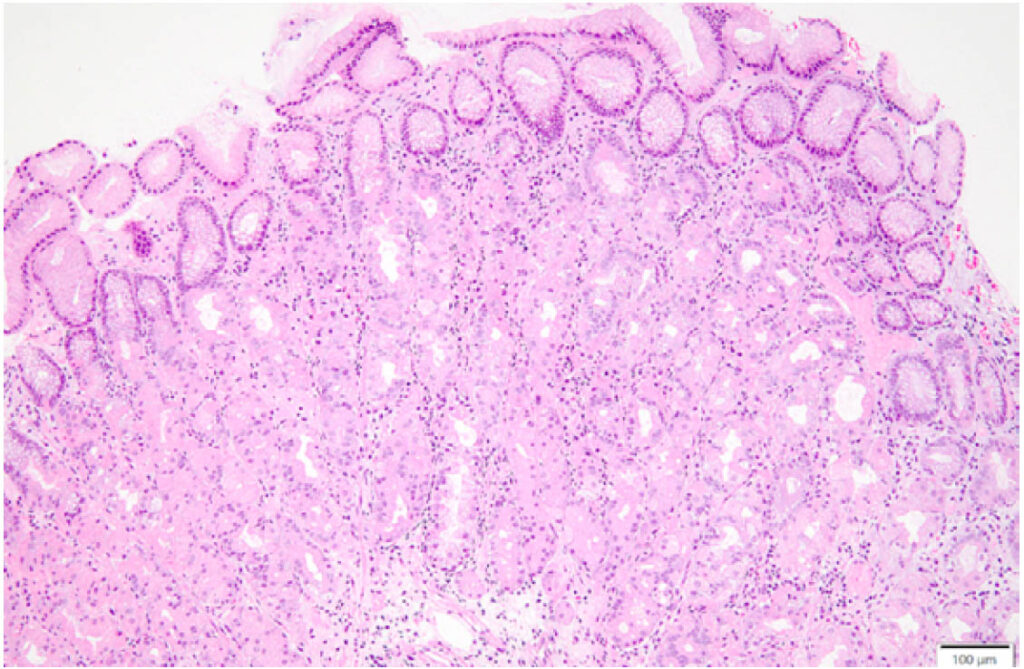

AIGの確定診断には組織診断が必須である。病理依頼時にはAIGを疑っている旨を明確に伝え,可能であればGastrinとChromogranin A染色を依頼する。本症例の胃体部ROM内部から採取された組織像は,壁細胞の変性,深部腺優位のリンパ球浸潤と第2層・第3層の不明瞭化を認め,典型的な早期AIGの組織所見を呈していた(下図)。